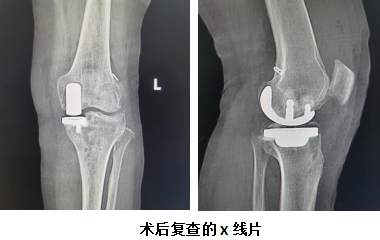

在与患者及家属沟通同意后,手术当日,由运动医学科庞军主任主刀,苏晨晨、李雄、贾燕龙医师协助,为患者成功实施了关节镜下微创前交叉韧带重建+内侧单髁置换手术。手术过程顺利,术后第二天,患者便能佩戴支具下地活动。